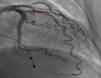

Case reportWe describe the case of a 73-year-old woman with acromegaly due to a pituitary adenoma diagnosed and treated surgically at the age of 38 but with recurrence and reoperation at the age of 50. She had a history of hypertension, multinodular goiter and atrial fibrillation under oral anticoagulation. She was referred to our cardiology department due to echocardiographic evidence of obstructive hypertrophic cardiomyopathy and a three-month history of progressively worsening exercise-induced dyspnea and orthopnea (NYHA class III) under optimal medical therapy. A complete echocardiogram revealed severe asymmetric hypertrophy of the left ventricle, mostly in the basal portion of the interventricular septum (19 mm), without LV dilation, depressed ejection fraction or wall motion abnormalities. There was also a dynamic LVOT obstruction gradient of 70 mmHg at rest and of 120 mmHg with Valsalva maneuver and systolic anterior movement (SAM) of the mitral valve with mild regurgitation and moderate to severe tricuspid regurgitation. A better characterization with magnetic resonance imaging confirmed basal interventricular septal hypertrophy without evidence of intramyocardial fibrosis (Figure 1). Genetic testing excluded the most frequent forms of familial hypertrophic cardiomyopathy. A 24-hour Holter examination revealed permanent atrial fibrillation but no ventricular repolarization or heart rate abnormalities. After a multidisciplinary discussion, ASA was performed, guided by myocardial contrast echocardiography, with injection of 2 cc of alcohol in the first septal branch of the left coronary artery (Figures 2–4). The procedure was uneventful and no atrioventricular (AV) conduction disturbances were detected. The one-year echocardiographic reassessment showed a reduction of the interventricular septum to 13 mm and of 8 mm in the region treated by ASA. The LVOT gradient was 28 mmHg at rest and the SAM of the mitral valve and the moderate to severe tricuspid regurgitation had disappeared. The patient improved significantly to mild-to-moderate heart failure (NYHA class I-II) and no major cardiovascular events were observed during follow-up.